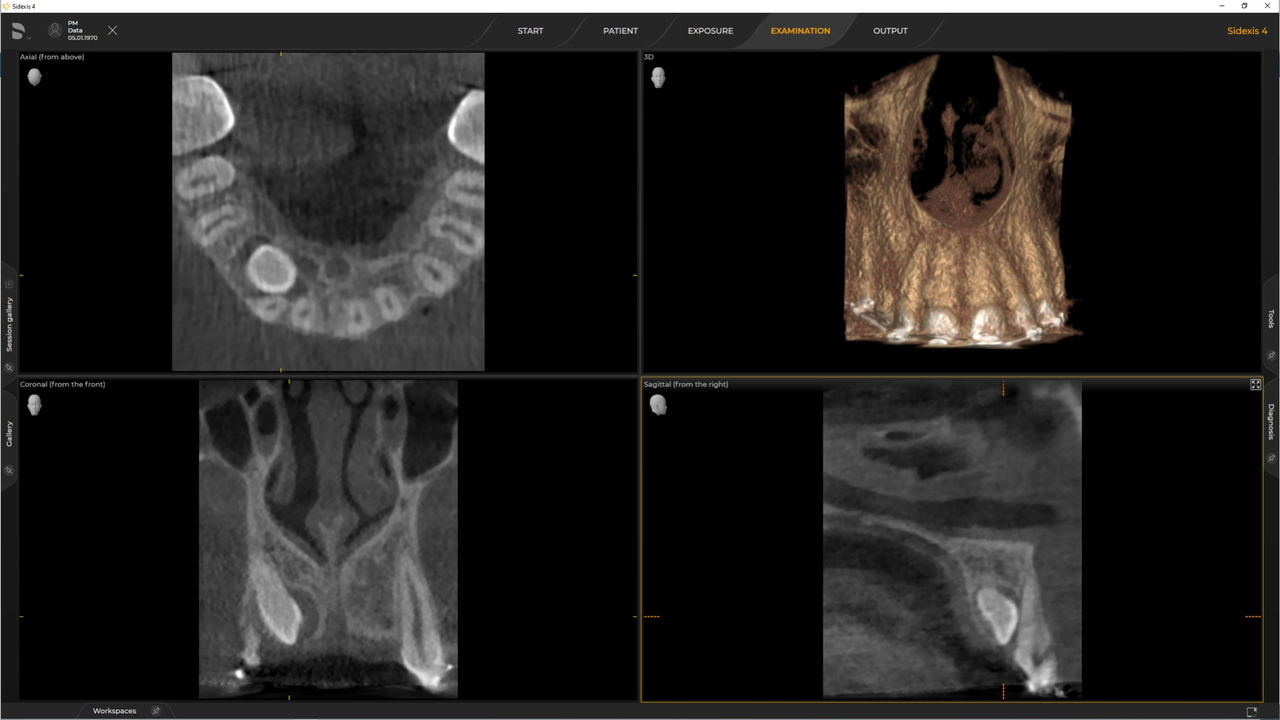

Met de 3D Intelligent Low Dose-modus krijgt u 3D-beelden in het dosisbereik van een 2D-röntgenfoto. In de HD-modus (maximaal 1400) worden afzonderlijke beelden vastgelegd tijdens een enkele rotatie en omgezet in een 3D-volume met maximaal 80 μm voor beelden in hoge resolutie met weinig verstoring.

Een breed scala aan volumegroottes om uw verschillende diagnostische en klinische behoeften te ondersteunen, van Ø 5 x 5,5 cm tot Ø 11 x 10 cm.